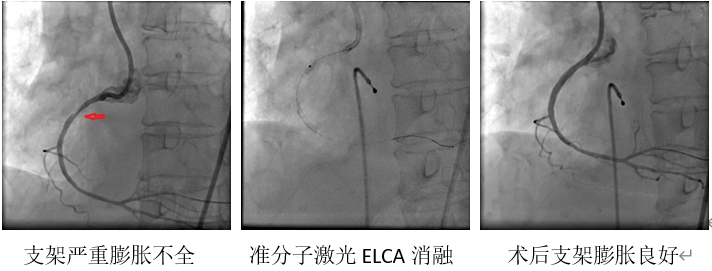

患者,女性,68岁,外院于右冠近段植入支架,释放后发现因血管钙化引起支架严重膨胀不全,多种方式处理均无效,患者频繁发作严重心绞痛。支架膨胀不全,极易引起支架内急性血栓形成,危及生命,亟需处理,为求进一步治疗,患者转入21点技巧中心

。目前世界上微创介入处理支架膨胀不全的技术手段不多,可用技术为准分子激光、震波球囊、旋磨支架,国内应用经验均少,右冠病变,尚不适合外科CABG,旋磨支架风险极高,可做为备选方案执行。张勇主任医师、刘仲伟副主任医师团队经过严谨预案,决定准分子激光处理严重支架膨胀不全(术中发现震波球囊无法通过严重支架膨胀不全处)。术中克服器械不能通过等重大困难,艰难送激光导管到位,给予间断消融,成功处理严重膨胀不全支架,术后患者症状缓解,危险解除,目前已安全出院。